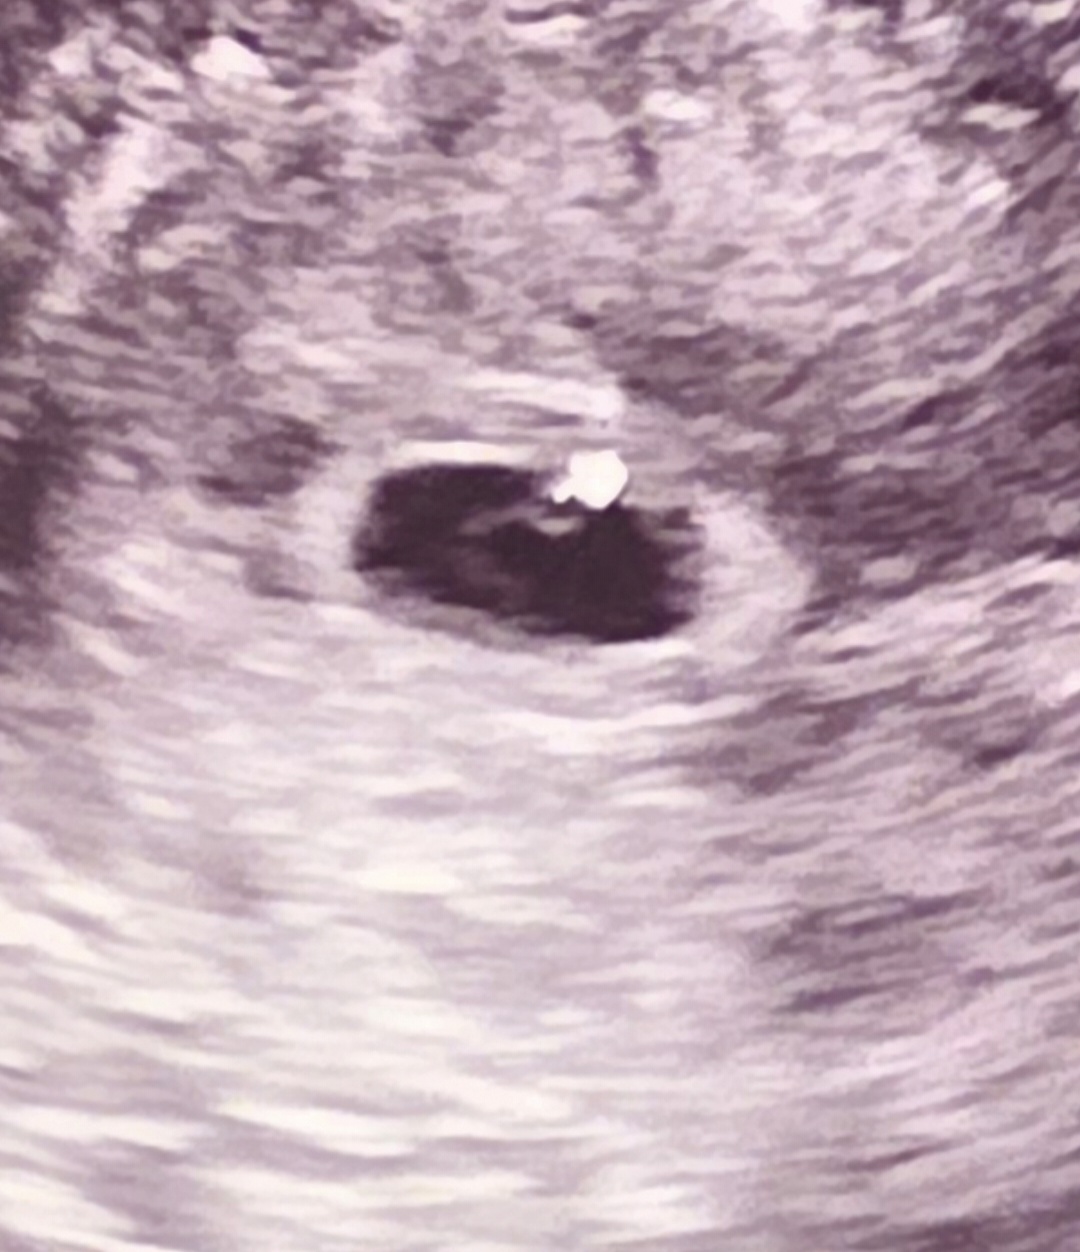

딱 5주때 (+17일) 난황까지 보고 왔는데 다른사람과비교하니 난황모양이좀 이상하네요..ㅜ 8일에 봤고 15일에 다음 초음파예약인데.. 목.금요일즘 동네병원가서 함 더봐볼까요..? 걱정이에요ㅜ

저도 주차로는 5주차 4일정도에 난황봤는데 아가집도 동그랗지 않고 난황도 저런느낌으로 보였어요 ㅎㅎ 다음주에 가서 한번 더 보려듀요!! 난황이 보이는 상태라 큰 문제가 있는건 아니라고 했어요!

난황모양이 동그랗게 커지는 건 더 시간이 지나야해요 난황을 봤으면 걱정하지 않으셔도 돼요